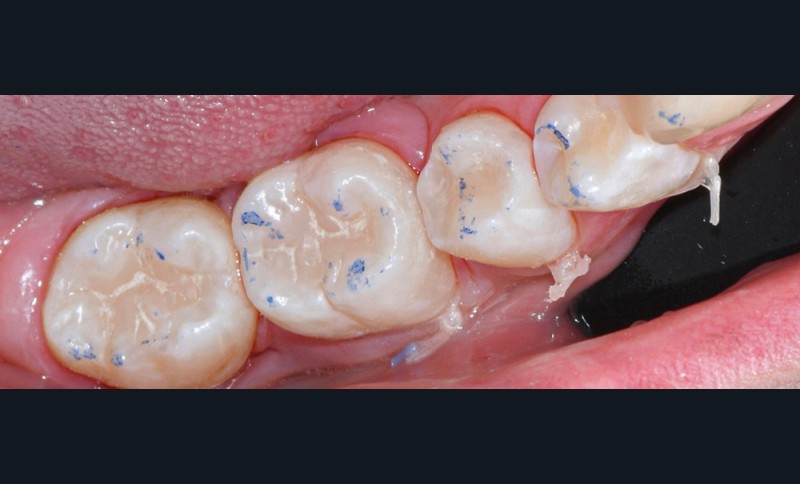

Nous détaillons la technique à travers le cas d’une jeune fille de 18 ans présentant des lésions carieuses sur quatre dents (fig. 1 à 14).